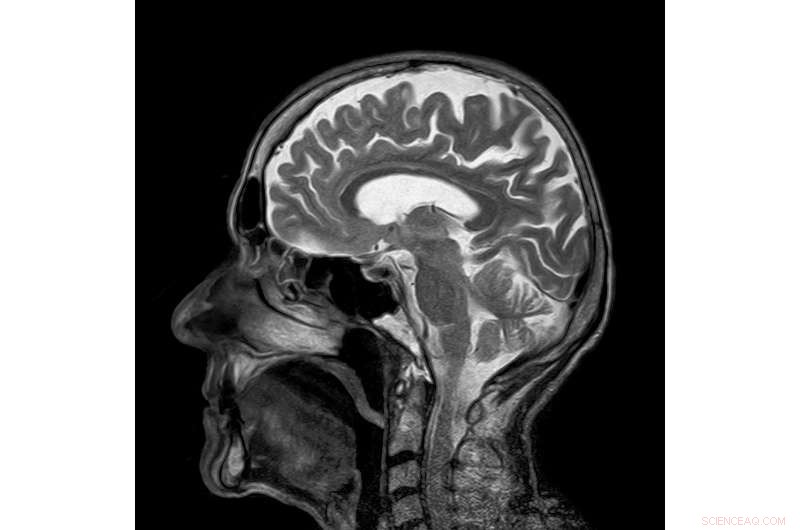

Credit: CC0 Public Domain

Researchers at Case Western Reserve University School of Medicine have developed a method that could make magnetic resonance imaging—MRI—multicolor. Current MRI techniques rely on a single contrast agent injected into a patient's veins to vivify images. The new method uses two at once, which could allow doctors to map multiple characteristics of a patient's internal organs in a single MRI. The strategy could serve as a research tool and even aid disease diagnosis.